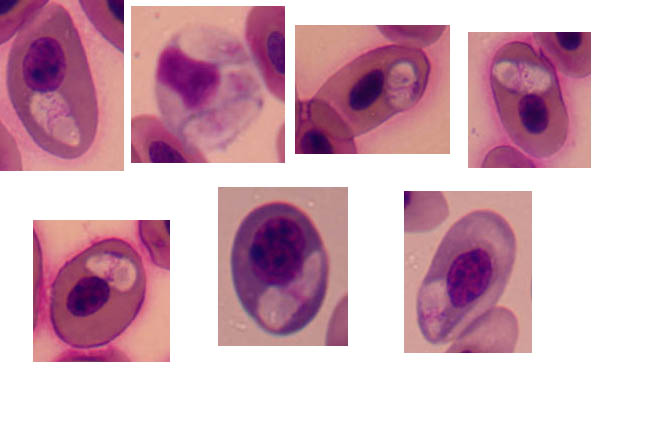

MALARIA EN LAGARTOS

MALARIA EN LAGARTOS: